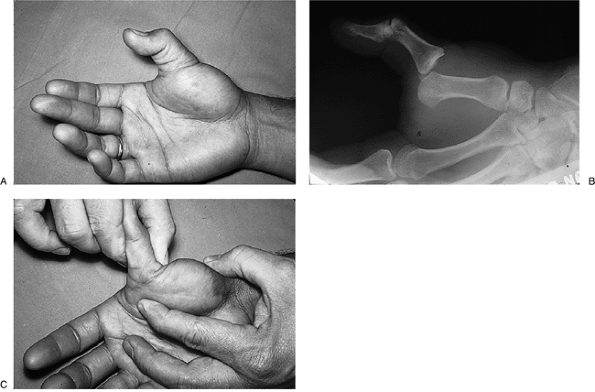

lesser incidence of collateral ligament rupture. Figure 10-8 depicts the x-ray appearance of reducible palmar dislocation.

Figure 10-8 X-ray appearance of a palmar dislocation of the PIP joint.

If an anterior dislocation can be

slip has occurred and requires appropriate treatment. -

It has been noted that palmar

(most often a tear of the central slip), a collateral ligament, and the

The associated ligament and tendon

PIP joint support, which is manifested by palmar subluxation,

Figure 10-9 Clinical and x-ray appearance of a neglected palmar dislocation of the ring finger PIP joint.-

Figure 10-9 demonstrates the clinical and x-ray appearance of such a neglected case involving the PIP joint of the ring finger.

Although the joint was reduced and soft tissue reconstruction was performed, the end result was a stiff finger.